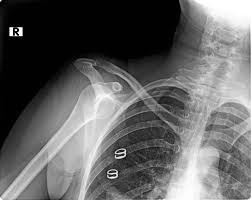

Omuz çıkığının 30 ile 50 yaş arasında, daha çok travma ve düşme kaynaklı oluştuğunu belirten Dicle Üniversitesi'nden Ortopedi ve Travmatoloji Uzmanı Doç. Dr. Mehmet Gem, bazı davranışların da omuz çıkığına yol açtığını söyledi.

Gem, "Esnerken, hapşırırken, elbise giyerken dahi omuz çıkabiliyor. Omuz ilk çıktıktan sonra omuz eklemi laçka hale geliyor. İlk çıkık sonrasında o bölgede omzu çevreleyen yumuşak dokuların, yapıların yaralanması sonucunda omuz çıkmaya artık alışıyor. Bu nedenle dikkatli olunmalı" diye konuştu.

Kireçlenme nedeni olabilir Doç. Dr. Gem, özellikle sürekli yapılan işlerde hastaların mağduriyet yaşadığına dikkati çekerek, kişilerin günlük iş ve aktivitelerini omuz çıkması nedeniyle zamanla yapamaz hale gelebildiğini, bunun da yaşamı olumsuz etkilediğini belirtti. Omuz çıkığının çevre yapılara zarar vererek ağrıya neden olduğunu aktaran Gem, sürekli omzu çıkan hastaların, birçok hareketi çekinerek yaptığını, bunun ilerleyen dönemlerde kireçlenmeye neden olduğunu vurguladı.

Omuz çıkığı kader değil, tedavi edilebilir Gem, hastalığın geçmişte omuz eklemi açılarak yapılan ameliyatla tedavi edildiğini, son yıllarda ise artroskopi adı verilen kapalı yöntemle başarılı sonuçlar alındığını dile getirerek bunun bazı avantajları olduğunu anlattı.

Kapalı yöntemle yapılan işlemde cerrahi bir müdahaleye gerek kalmadığını vurgulayan Gem, "Kapalı yöntemde birer santimetrelik kesilerle hastanın şikayetleri gideriliyor. Hastanede kalma süresi de kısalıyor. Estetik açıdan da daha başarılı sonuç veriyor. Bu yöntem son iki yıldır Dicle Üniversitesi Ortopedi Kliniği'nde uygulanıyor" ifadesini kullandı. Gem, omuz çıkığının kader gibi algıladığını belirterek "Bu rahatsızlık kader değil, kapalı yöntem ile tedavisi mümkün" dedi.